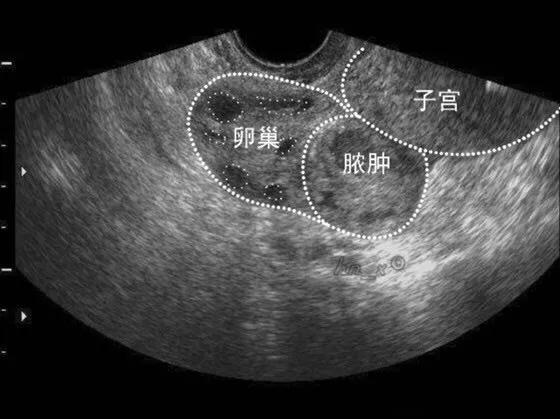

一个普通的工作日,妇科病房里一如往常的忙碌着。 突然,平车推进来一位的中年妇女,面容痛苦,双手按住自己的下腹部,不停的*吟呻**着。意识到病人病情的危重性,妇科立即启动妇科急诊流程。 急查血常规、急诊生化、凝血功能,急诊床边B超......”“心电监护,开放静脉通路......”医嘱一条条飞速下达,护士也迅速的处理着。 辅助检查回报:急诊床边B超提示:左侧附件区可探及混合型回声团块,范围约101*68*72mm,周边可见点状血流信号。尿妊娠试验阴性。血常规:中性粒细胞比率 89%。患者腹痛明显,有手术指征,即可拟“腹痛待查:卵巢脓肿?卵巢囊肿蒂扭转?”行手术治疗。

患者手术指征明确,于2020年2月18日在全麻下行腹腔镜探查。术中见:肠管、大网与腹前壁广泛致密粘连,仅脐周及两侧盆壁少量间隙,盆腔封闭。术中诊断:双侧输卵管卵巢积脓、盆腔脓肿、肠粘连、盆腔粘连。